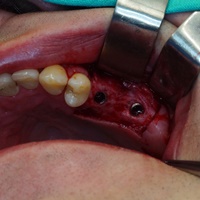

Odbudowa kosci wyrostka zębodołowego żuchwy, odbudowa dziąsła, wydłużenie koron klinicznych górnych przedtrzonowców, implantacja.